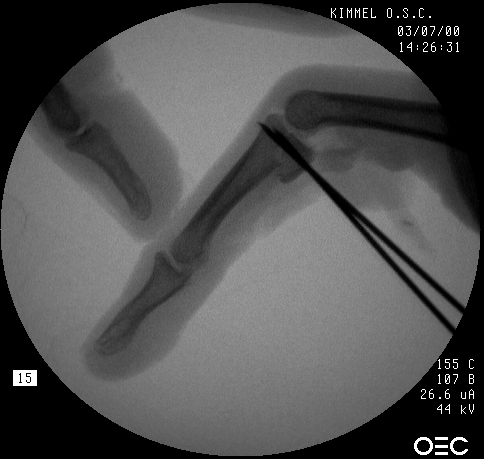

In the operating room, the crushed bone is removed and provisional fixation of the volar graft is obtained with Kirschner wires.

These wires are then replace, one at a time with micro screws.